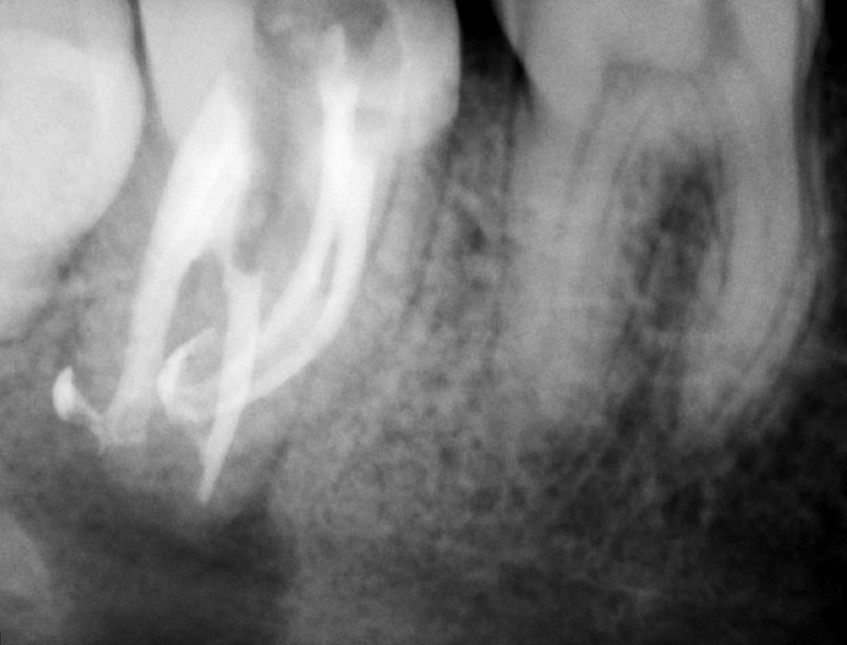

L’utilisation du scanner, et maintenant du CBCT, bouleverse l’idée très radiographique que nous avions du système canalaire.

En effet, la culture endodontique, fondée sur les critères radiographiques, a fait oublier les études de Hess et Zurcher (1925) qui mettent en évidence la complexité du système endo-canalaire [1]. Ce système présente une cavité principale (par exemple, le canal principal) ainsi que des canaux accessoires/latéraux. 25 % de ces microcanaux peuvent être interconnectés les uns aux autres, avec une densité plus importante de ramifications dans la région apicale du canal principal [2].

Endal, en 2011, montrait également, en utilisant le micro CT Scanner, l’insuffisance de nettoyage des isthmes inter-canalaires à nos techniques conventionnelles [19]. L’utilisation du laser Er:YAG devenait alors incontournable dans le nettoyage de ces isthmes et des zones non instrumentées (fig. 2 et 3).

L’anatomie complexe du système canalaire et la pénétration difficile des irrigants [26] limitent la capacité de nettoyer, débrider, et désinfecter en trois dimensions le réseau endodontique.